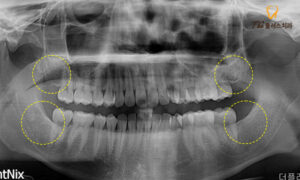

하지만 양쪽 아래 사랑니의 경우

잇몸뼈 안에 묻혀있는 매복 사랑니의 형태이며,

특히 왼쪽 아래의 사랑니의 뿌리를 보시면

휘어있는 모습이 관찰됩니다.

이렇게 환자분의 경우처럼

매복되어 있을 뿐만 아니라

뿌리가 휘어진 사랑니의 경우,

발치 시 일부 잇몸의 절개가 필요하며,

뼈 삭제가 동반되기도 합니다.

또한 휘어진 뿌리가 발치하는 과정에서

부러질 경우가 있을 수 있어

좀 더 신경 써야 하는 까다로운

진료에 속하는데요.

발치 후의 엑스레이 상에서

꽤 난이도가 있는 발치였음에도 불구하고

남아있는 잔여 조직 없이

깔끔하게 발치된 모습을 보실 수 있습니다.